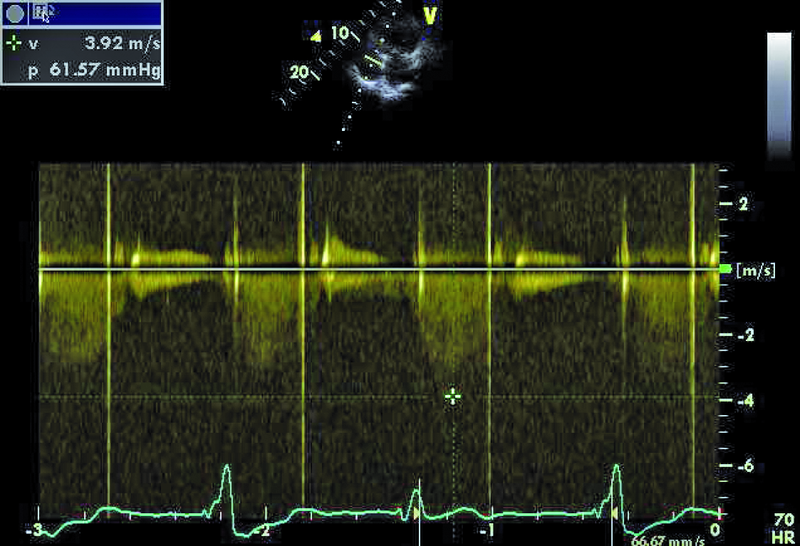

3. Podwyższone gradienty przepływu przez sztuczną zastawkę aortalną (ryc. 3).